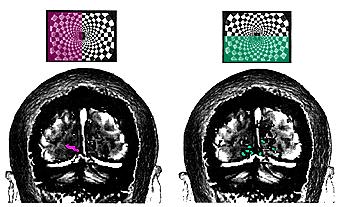

BLOOD FLOW variations in the visual cortex demonstrate how a subject's brain responds to a pattern being viewed. The colors in this image show the cortical activity corresponding to the subject's view of either half of the pattern. This activity is a neural correlate of visual experience, but the relationship between the two remains mysterious.